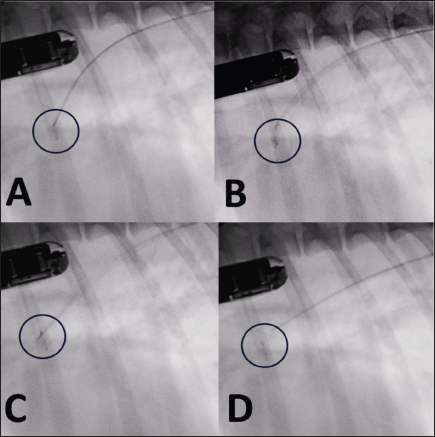

Fig. 4. Fluoroscopic sequence. (A) The first disc is deployed and the entire system is retracted until it engages the pulmonary ostium. (B) The second and third discs are released into the ampulla. (C) The device is released with anticlockwise rotation of the delivery cable. (D) The delivery catheter is removed along with the delivery cable.

The delivery wire and catheter were gently withdrawn until resistance was experienced in the pulmonary ostium. The guiding sheath was then retracted, allowing expansion of the central and proximal discs of the device within the PDA ampulla.

The stability of the device was subsequently tested with the push–pull “Minnesota wiggle” maneuver, and the cessation of transductal flow and the correct positioning of the device was verified using TEE (Figs. 4 and 5). The device was then deployed by rotating the delivery cable counterclockwise with the appropriate plastic vise. To verify the closure of the PDA and the absence of protrusions in the aorta further, a second angiography was performed as before (Fig. 6).